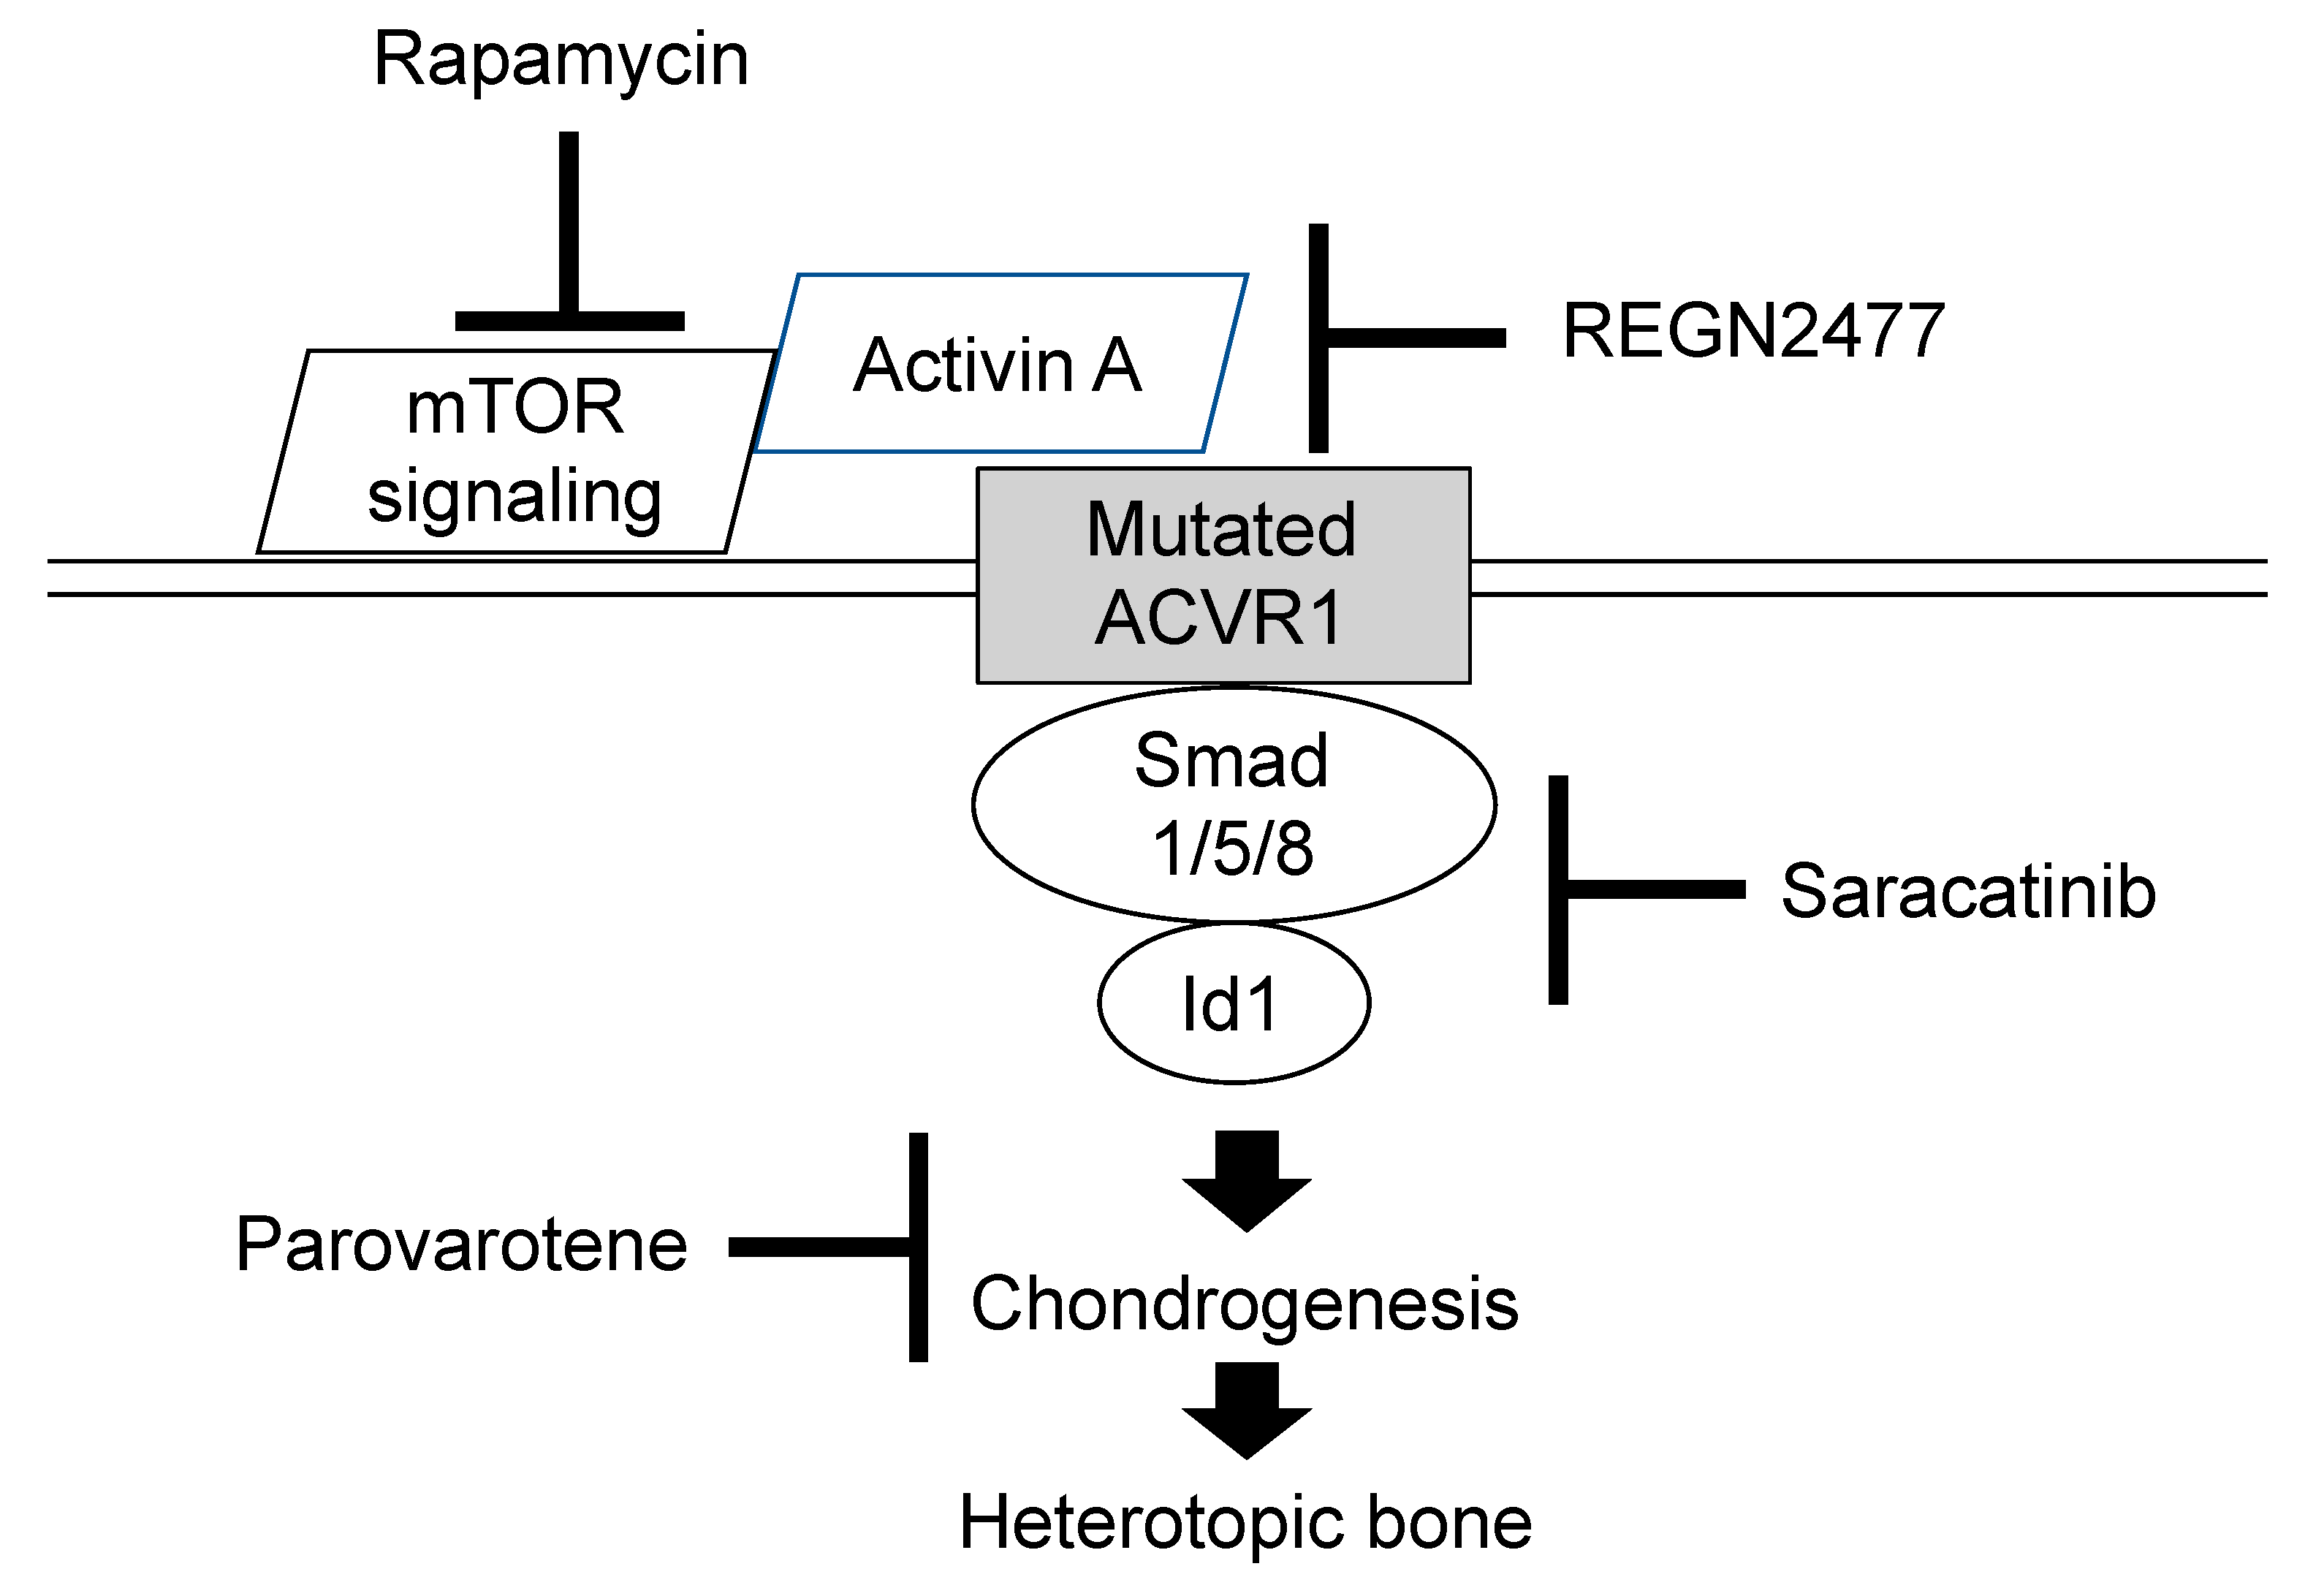

- Cappato, S.; Giacopelli, F.; Ravazzolo, R.; Bocciardi, R. The horizon of a therapy for rare genetic diseases: A “druggable” future for fibrodysplasia ossificans progressiva. Int. J. Mol. Sci. 2018, 19, 989. [Google Scholar] [CrossRef] [PubMed] [Green Version]

- Katagiri, T.; Tsukamoto, S.; Nakachi, Y.; Kuratani, M. Recent topics in fibrodysplasia ossificans progressiva. Endocrinol. Metab. 2018, 33, 331–338. [Google Scholar] [CrossRef]

- Wentworth, K.L.; Masharani, U.; Hsiao, E.C. Therapeutic advanced for blocking heterotopic ossification in fibrodysplasia ossificans progressiva. Br. J. Clin. Pharmacol. 2019, 85, 1180–1187. [Google Scholar] [CrossRef]

- Hino, K.; Zhao, C.; Horigome, K.; Nishio, M.; Okanishi, Y.; Nagata, S.; Komura, S.; Yamada, Y.; Toguchida, J.; Ohta, A.; et al. An mTOR signaling modulator suppressed heterotopic ossification of fibrodysplasia ossificans progressiva. Stem Cell Rep. 2018, 11, 1106–1119. [Google Scholar] [CrossRef] [PubMed] [Green Version]

- Hino, K.; Horigome, K.; Nishio, M.; Komura, S.; Nagata, S.; Zhao, C.; Jin, Y.; Kawakami, K.; Yamada, Y.; Ohta, A.; et al. Activin-A enhances mTOR signaling to promote aberrant chondrogenesis in fibrodysplasia ossificans progressive. J. Clin. Investig. 2017, 127, 3339–3352. [Google Scholar] [CrossRef] [Green Version]